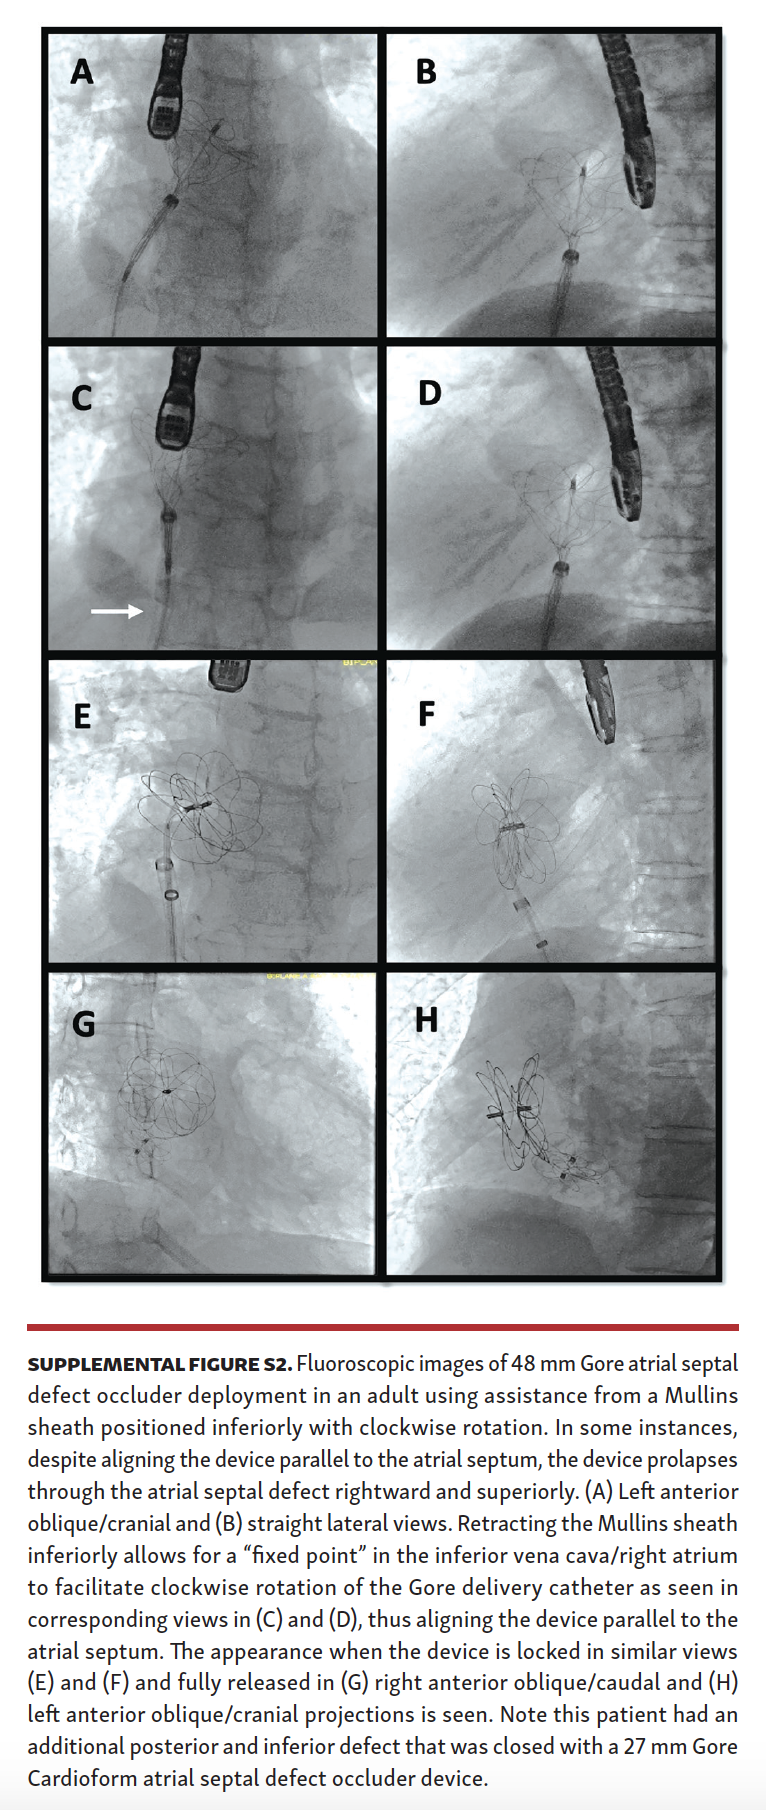

A total of 98 patients underwent attempted ASD closure during the study period (70 patients from the Gore ASSURED Clinical Study-Pivotal and Continued Access studies) and 28 patients after the study period. Of these patients, 52 underwent attempted secundum ASD closure using a long Mullins sheath (Supplemental Figures S1 and S2), while 46 patients underwent attempted secundum ASD closure with the Gore Cardioform delivery catheter through a short sheath in standard fashion.

Mullins-sheath facilitated Gore Cardioform ASD occluder delivery technique. The mechanism of favorable exaggeration of the angle of the Gore Cardioform ASD occluder delivery system when used with a Mullins sheath is seen in Figure 1. In large defects or in defects with deficient rims, the angulation of the Gore delivery catheter may not allow for alignment of the device parallel to the atrial septum, with resultant device prolapse superiorly through the defect into the right atrium (Figure 2). In such situations, the short sheath was exchanged for an appropriately sized 63 cm-long or 75 cm-long Mullins sheath in the left atrium and the dilator and wire were removed (same Fr size as required short sheath Fr size). When used in combination with a Mullins sheath, the angulation is exaggerated enough to facilitate better alignment parallel to the atrial septum (Figure 3). The Mullins sheath was rotated clockwise to assume a posterior orientation to align the device parallel to the atrial septum as it was being delivered. The Gore Cardioform ASD occluder delivery catheter was then advanced through the Mullins sheath, which was positioned with continuous clockwise rotation, often by the assistant, as the primary operator deployed the device. In some cases, despite this maneuver, the device was not aligned parallel to the atrial septum. In such cases, once the left atrial side of the device was deployed and aligned in the best possible way, the Mullins sheath was withdrawn (if 63 cm-long sheath was used) to the inferior vena cava or right atrium to serve as a “fixed point,” whereby further clockwise rotation of the Gore delivery catheter could be performed if needed to facilitate further device alignment as parallel to the atrial septum as possible (Figure 4). In some cases, the Gore delivery catheter was rotated 180° clockwise despite the use of the Mullins sheath to facilitate capture of the aortic and superior vena cava rims. Use of the Mullins sheath also facilitated delivery of the device when inferior disc prolapse into the left atrium was encountered (Figure 5). Finally, in some cases, the tip of the Gore Cardioform ASD occluder delivery catheter was also hand-shaped to further exaggerate its angle. The use of the Mullins sheath was at the discretion of the implanting physician.